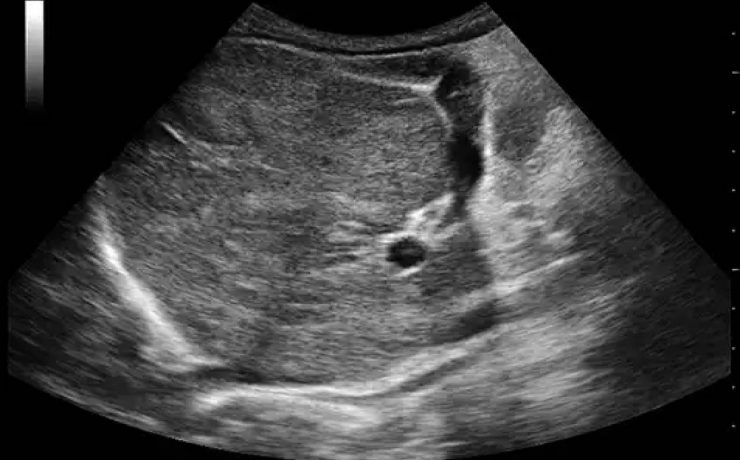

Alteraciones segundo trimestre de gestación.

Objetivo determinar la asociación entre ausencia e hipoplasia del hueso nasal fetal y alteraciones estructurales y/ o cromosómicas en el neonato, en la población en general en el ultrasonido del segundo trimestre. La gran mayoría de malformaciones congénitas no son prevenibles ya que constituyen accidentes en la organogénesis embrionaria y